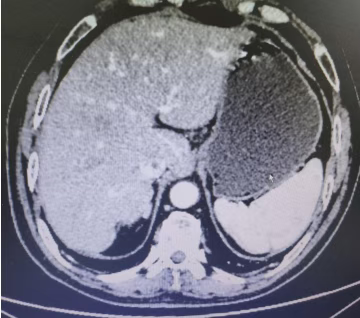

Abdominal CT films from February 23, 2023 (2 images)

The patient subsequently returned for re-examinations every six months until February 23, 2023. The condition remained stable, with no evidence of neoplastic lesions. The patient's mental state is good, and daily farm work is unaffected, bringing new hope to the family.

This patient with advanced gastric cancer, through standardized chemotherapy, good compliance, and an optimistic mindset, has achieved a survival period of over 5 years. Currently, the patient's physical condition is good, having reached clinical cure for the tumor, far exceeding the expectations of both doctors and the patient.